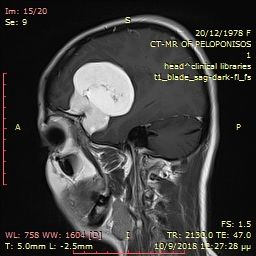

Pre-operative brain meningioma

Angiography with preoperative embolization of the meningioma.